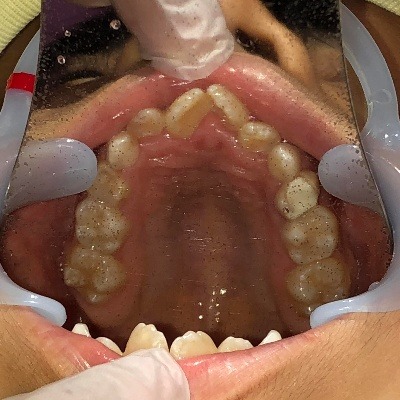

上顎

| 治療内容 | インビザライン・ファースト |

|---|---|

| 治療詳細 | 反対咬合や叢生、開咬を整えるために、歯の表面にアタッチメント(白い突起)をつけました。 また、顎間ゴムと呼ばれる引っ掛けるゴムの補助装置も用いて治療を行いました。 |

| 治療期間 | 2023.10.3~2025.4.7 来院回数:14回 |

| 治療費用 | 検査代 0円 矯正代 150,000円 (税込165,000円) 保定代 40,000円 (税込44,000円) |